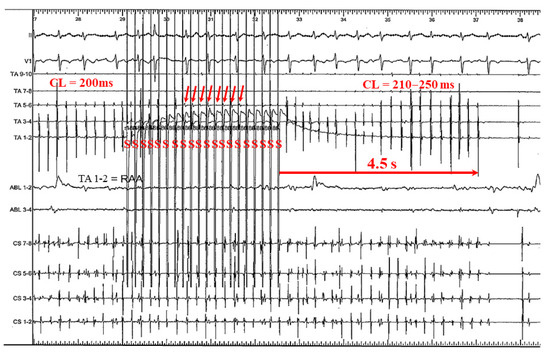

3.2.1. Case 1: 42-Year-Old Man with Symptomatic PAF